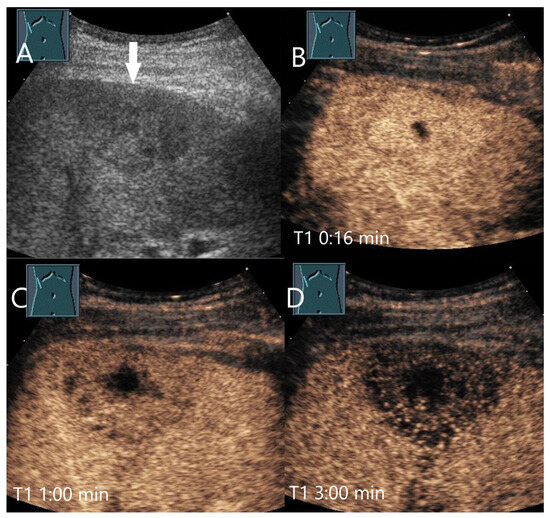

Figure 9.

Chronic pyogenic liver abscess. Patient with hypoechoic lesion (arrow) with high inflammatory laboratory (A). CEUS shows mild arterial hyperenhancement after 16 s (B), with mild washout after 1 min (C) and progressive washout after 3 min (D). The US-guided biopsy revealed the histologic diagnosis of a chronic granulocytic sclerosing inflammation.